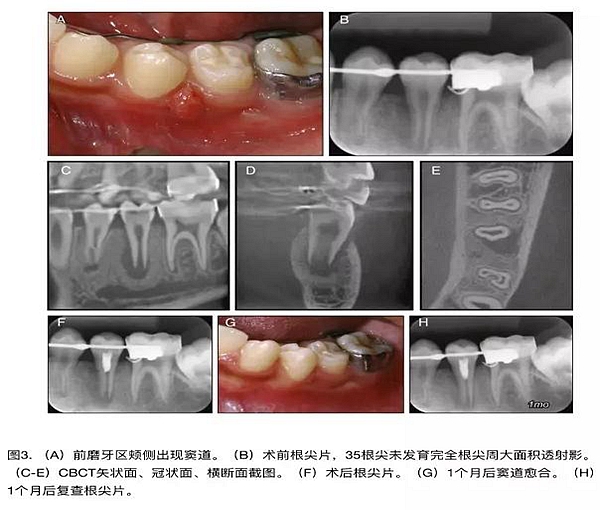

原則上年輕恒牙的牙髓治療應(yīng)盡可能以保存活髓的方式以便不影響牙根繼續(xù)發(fā)育。本文3個(gè)病例均描述了根尖尚未發(fā)育完成的下頜前磨牙被確診為牙髓壞死伴有大面積根尖病損,治療過程中在根管內(nèi)發(fā)現(xiàn)了部分活髓,而采用活髓切斷后都取得了很好的療效。